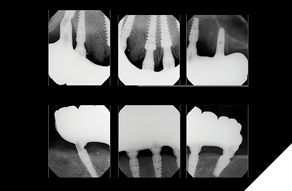

The patient returned 2 months later (due to patient scheduling delays) and the maxillary and mandibular Nexus restorations were inserted (Figs. 26A-C). Passive seating of the restorations were confirmed with the Sheffield test and radiographic confirmation. The occlusion was checked and final radiographs taken (Fig. 27).

Fig. 27